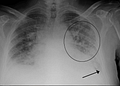

acute pulmonary edema

Phù phổi cấp là tình trạng ngạt thở cấp do nước ra ngoài mao mạch phổi quá nhiều gây nên phù phổi.